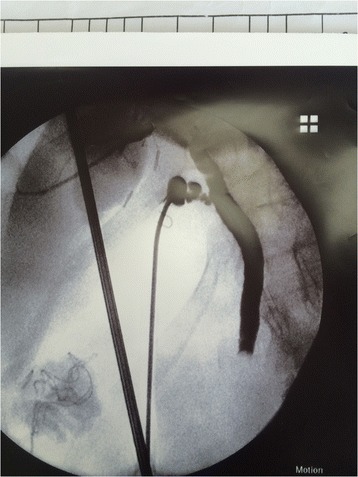

Fig. 3.

Choledocotomy technique and extraction of big CBD stone

This approach was used either after failed trial of cannulation of cystic duct or failed stone extraction through cystic duct, in three patients, we employed it without trying the trans-cystic technique because they were post failed ERCP due to big impacted stones. IOC was done through CBD puncture with lumber needle which showed CBD stones. In these cases we converted to choledochotomy in which the CBD was exposed and a vertical ductotomy was done on the anterior surface of the duct below the junction between cystic duct and CBD (Fig. 3). The techniques for stone clearance are identical to the trans-cystic approach. Through the choledochoscope, flushing with saline was done under pressure to facilitate clearance of small stones. Dormia basket and/or balloon catheter can be also used to pull stones to the abdominal cavity then to be retrieved outside (Fig. 4). The choledochotomy was closed over a T-tube in nine cases and over an antegrade stent in 10 cases; the stent was inserted through the site of cholodotomy under guidance of fluoroscopy for removal by ERCP later. Primary closure of the CBD was done in the remaining seven patients with absorbable suture. External tube drains were used only when we perform choledochotomy technique and not used in trans-cystic technique.